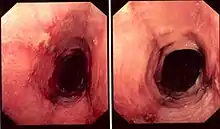

Endoscopic image of lymphocytic esophagitis, demonstrating narrow lumen esophagus (left), linear furrows (right) and esophageal rings (right)

The diagnosis of lymphocytic esophagitis is made by biopsy of the mucosal lining of the esophagus. This is typically achieved at the time of esophagogastroduodenoscopy, a medical procedure wherein an endoscope is inserted through the mouth, into the esophagus, in order to visualize and biopsy the mucosa.

While the diagnosis of lymphocytic esophagitis depends on the biopsy results, certain changes can be visualized directly at the time of endoscopy. The esophagus may be narrow in calibre,[5] may show multiple rings,[5] redness,[5] linear furrows[1] or the mucosal lining may slide demonstrating a "crepe-paper" appearance.[1] Complications such as strictures of the esophagus can also be detected with endoscopy.[5] These changes are very similar to those found in eosinophilic esophagitis, a more common and better understood esophageal disorder thought to be of allergic origin.[5] Narrow-band imaging with magnification endoscopy is another imaging modality that can show characteristic changes of lymphocytic esophagitis.[7]